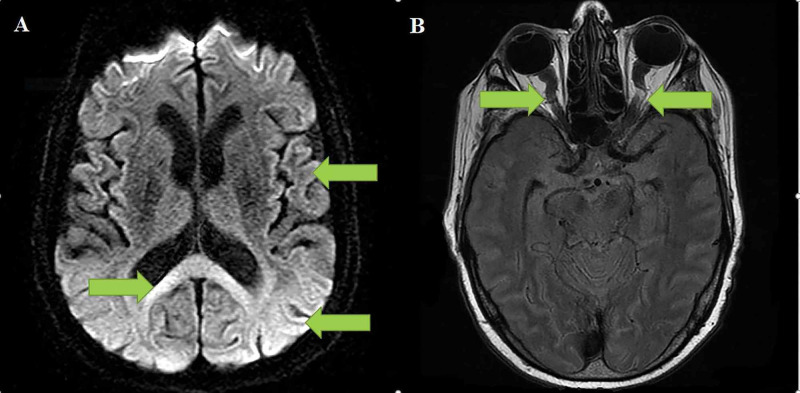

A man hospitalized with COVID-19 developed significant neurological manifestations (acute stroke-like symptoms) between 21-26 days post infection which were later confirmed with magnetic resonance imaging (MRI), showing changes typical of raised intracranial pressure and significant diffusion restriction suggestive of cytotoxic or excitotoxic, transient oedema secondary to inflammation and severe hypoperfusion state (Figures 1A and 1B).

Figure 1. 1A demonstrates severe diffusion restriction in the brain's subcortical regions and the splenium; 1B demonstrates the tortuous optic nerve sheath secondary to intracranial hypertension.

Arrow A demonstrates the severe diffusion restriction throughout the subcortical region and the splenium. Arrow B demonstrate the tortuous optic nerve sheath secondary to intracranial hypertension.

An MRI of the brain was performed on day 32 that showed generalized cortical diffusion restriction, which was also present in the supra- and infratentorial white matter (Figure 1A).

A few scattered microbleeds in the frontal, parietal and temporal lobe were described along with a small volume subarachnoid haemorrhage in the right frontal lobe (not shown). There was no pachymeningitis noted, and neither were there any signs of venous nor arterial occlusion. The same MRI also revealed the typical features of intracranial hypertension in the appearance of optic nerve sheath distension and tortuosity (Figures 1A-1B) and transverse sinus narrowing and empty sella turcica (not shown in image). No intracranial masses were noted.